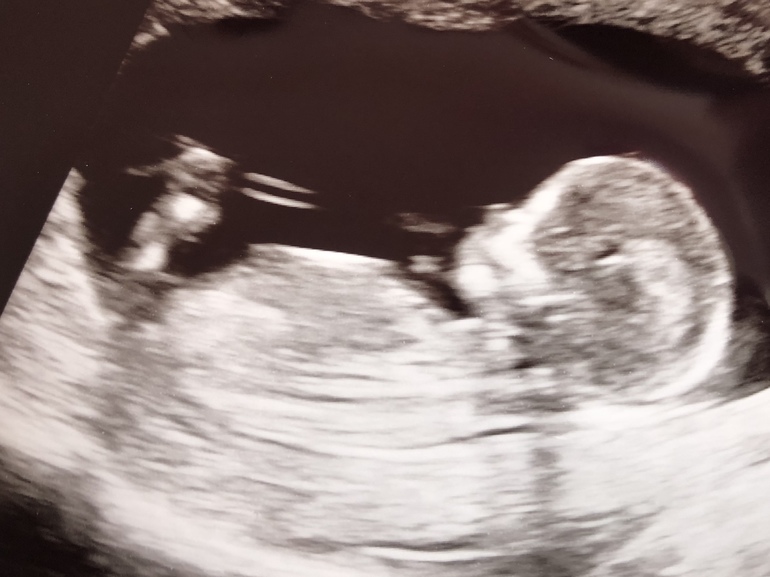

БеременностьСегодня был первый скрининг, который порадовал здоровьем малыша и малыми рисками на все бяки 😊

Малыш здоровый, активный и бодрый :) его все врач хвалила, мол как правильно сразу лёг, какой молодец))

Оказалось возраст на недельку побольше - 14 уже!

Пс: на фото будто улыбается)